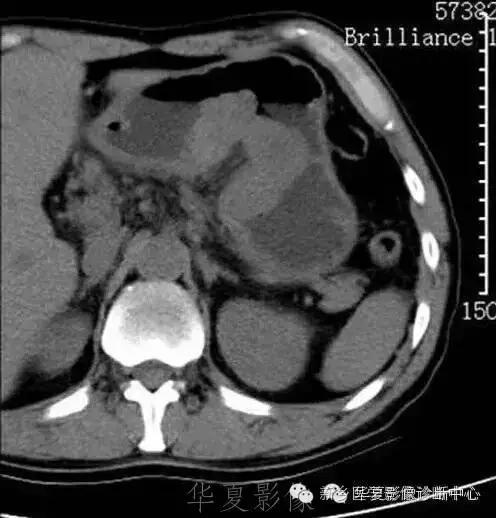

肝脏黑色素瘤

原发于肝脏的恶性黑色素瘤极其罕见。肝脏原发恶性黑色素瘤临床表现及体征均无特征性,与其他肝脏占位性、 肿瘤性病变无法区分,此为该病的临床特征。

肝脏恶性黑色素瘤的超声和 CT多表现为肝脏增大,肝内单发、 多发占位病变或弥漫性、 结节性改变, 占位性病变可为实性、 囊性、 囊实性改变,但上述改变无明显特异性, 与其他肝脏恶性肿瘤无法区分。MR T1 加权呈高信号、 T2 加权呈低信号